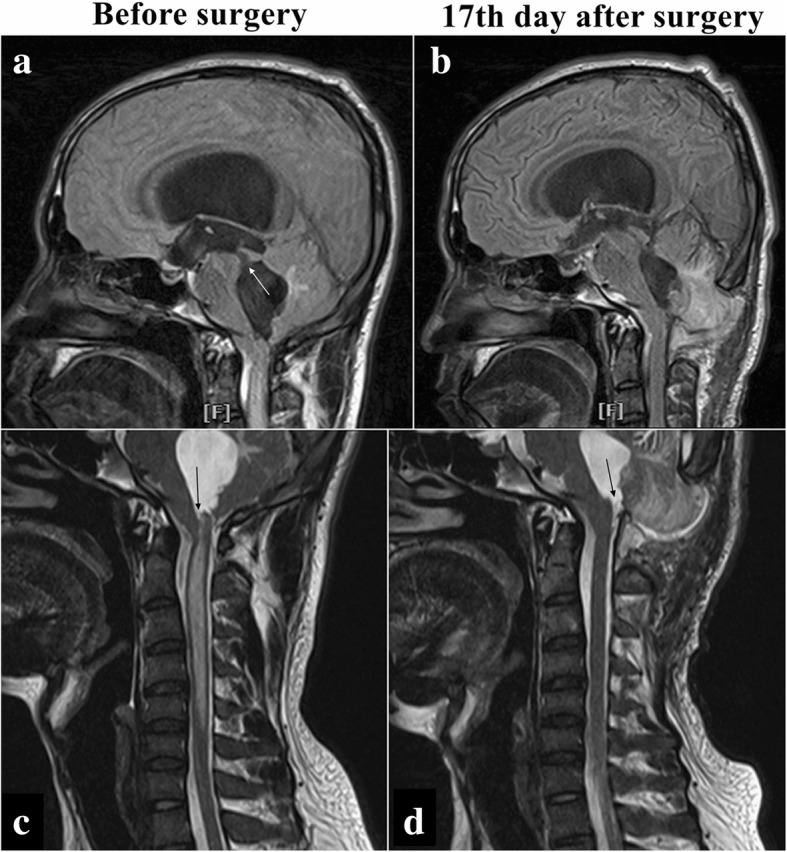

A 24-year-old Han Chinese man presented with a 2-month history of headache and dizziness accompanied by progressive loss of vision in both eyes. His symptoms worsened after a cervical massage 1 week before admission. He had frequent paroxysmal headache associated with nausea, vomiting, and blurred vision. He had a history of mumps and viral encephalitis at the age of 4, which had no sequelae. He had received no past interventions. He had no other medical, family, or psychosocial history. On admission, his visual acuity was 0.5 in both eyes. Physical examination showed bilateral severe optic papilledema, forced head position, and bilateral Babinski’s signs. MRI (Figs. 2 and 3) revealed hydrocephalus with a remarkably enlarged fourth ventricle, crowded posterior fossa, and syringomyelia extending from C1 to C5. His Evans index was 0.4 (61.30/152.9). He underwent a suboccipital and C1 decompression and duraplasty. After the operation, his headache and dizziness were relieved rapidly, and both Babinski’s signs disappeared. On the 17th postoperative day, his visual acuity reached 1.2 in the right eye and 0.6 in the left eye, and his bilateral optic papilledema was reduced. MRI (Figs. 2 and 3) showed that the fourth ventricle had become smaller, the trumpet-like aqueduct had become tubular, and the syringomyelia had dramatically disappeared. His Evans index dropped to 0.36 (55.16/151.96). At his 20th-week follow-up, his visual acuity had reached 1.5 in the right eye and 1.2 in the left eye. At his tenth-month follow-up, his vision in both eyes had reached 1.5, and the volume of the ventricular system had further decreased on MRI. His Evans index had dropped to 0.34 (51.5/149.3). He had no discomfort.

Fig. 3.

Disproportionately large communicating fourth ventricle coexisting with syringomyelia in patient 2. a-c Sagittal images of the fourth ventricle. c–d Sagittal images of syringomyelia. White arrow points to the dilated aqueduct (a); black arrow indicates the dilated central canal of the spinal cord communicating with the fourth ventricle (c); and black arrow points to the reopened outlet of the fourth ventricle (d)

Both of our patients were DLCFV. Patient 1 presented with a tetraventricular hydrocephalus that returned to normal after shunting the lateral ventricle, which indicated that the aqueduct had been patent or reopened due to the disappearance of the pressure gradient between the supratentorial and infratentorial compartments. Patient 2 presented with not only tetraventricular hydrocephalus but also syringomyelia and crowded posterior fossa, which fulfilled the concept of isolated rhombencephalic ventricle or holoneural canal dilatation proposed by Qi and Abbott [14]. The dramatic regression of patient 2’s clinical and radiological signs shortly after posterior fossa decompression proved the functional obstruction of the outlets, which was in accord with the definition of DLCFV and prompted the role of the crowded posterior fossa in the pathophysiology of DLCFV.

Patient 1 was a typical case of DLCFV without crowded posterior cranial fossa or other abnormality. She was cured successfully with a supratentorial VP shunt. However, the decision-making of the treatment strategy of patient 2 has been a puzzle. He had a crowded posterior fossa and cervical syringomyelia, which could have led to the obstruction of the outflow of CSF from the fourth ventricle. Because it has been proved that the DLCFV is not always responsive to VP shunt and the supratentorial CSF shunt, especially the low-pressure shunt system would increase the risk of upward herniation of the cerebellar tissue. Thus, in view of the obviously crowded posterior fossa and the syringomyelia, the posterior fossa decompression with duraplasty turned into the option of initial management. Although the major cerebellar ptosis could not be considered as a good imaging outcome, patient 2 obtained a good clinical outcome. The effectiveness of posterior fossa decompression to treat postshunt IFV has been reported [3]. Our cases suggested that posterior fossa decompression could be a choice for the initial management of the DLCFV coexisting with crowded posterior cranial fossa or syringomyelia.